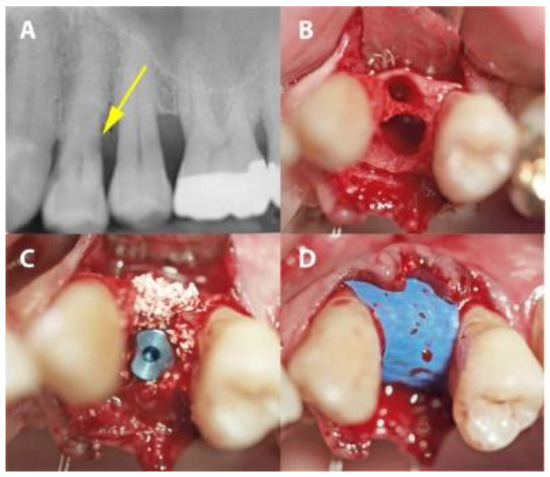

2.2. Surgical Procedure